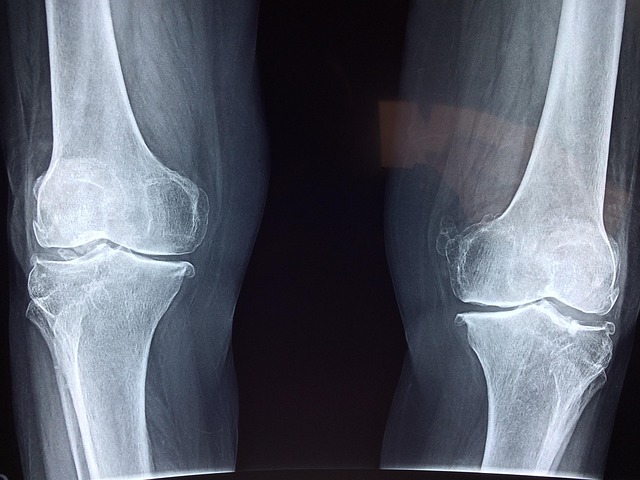

40대 이후 관절이 뻐근하고 무릎이 시큰거리는 느낌, 다들 한 번쯤 겪어보셨을 거예요.

🦴 40대 이후 관절이 약해지는 이유

- 노화로 연골이 마모되고 관절액이 줄어들면서 마찰 증가

| 무릎 | 걷거나 계단 오를 때 통증, 뻣뻣함 |